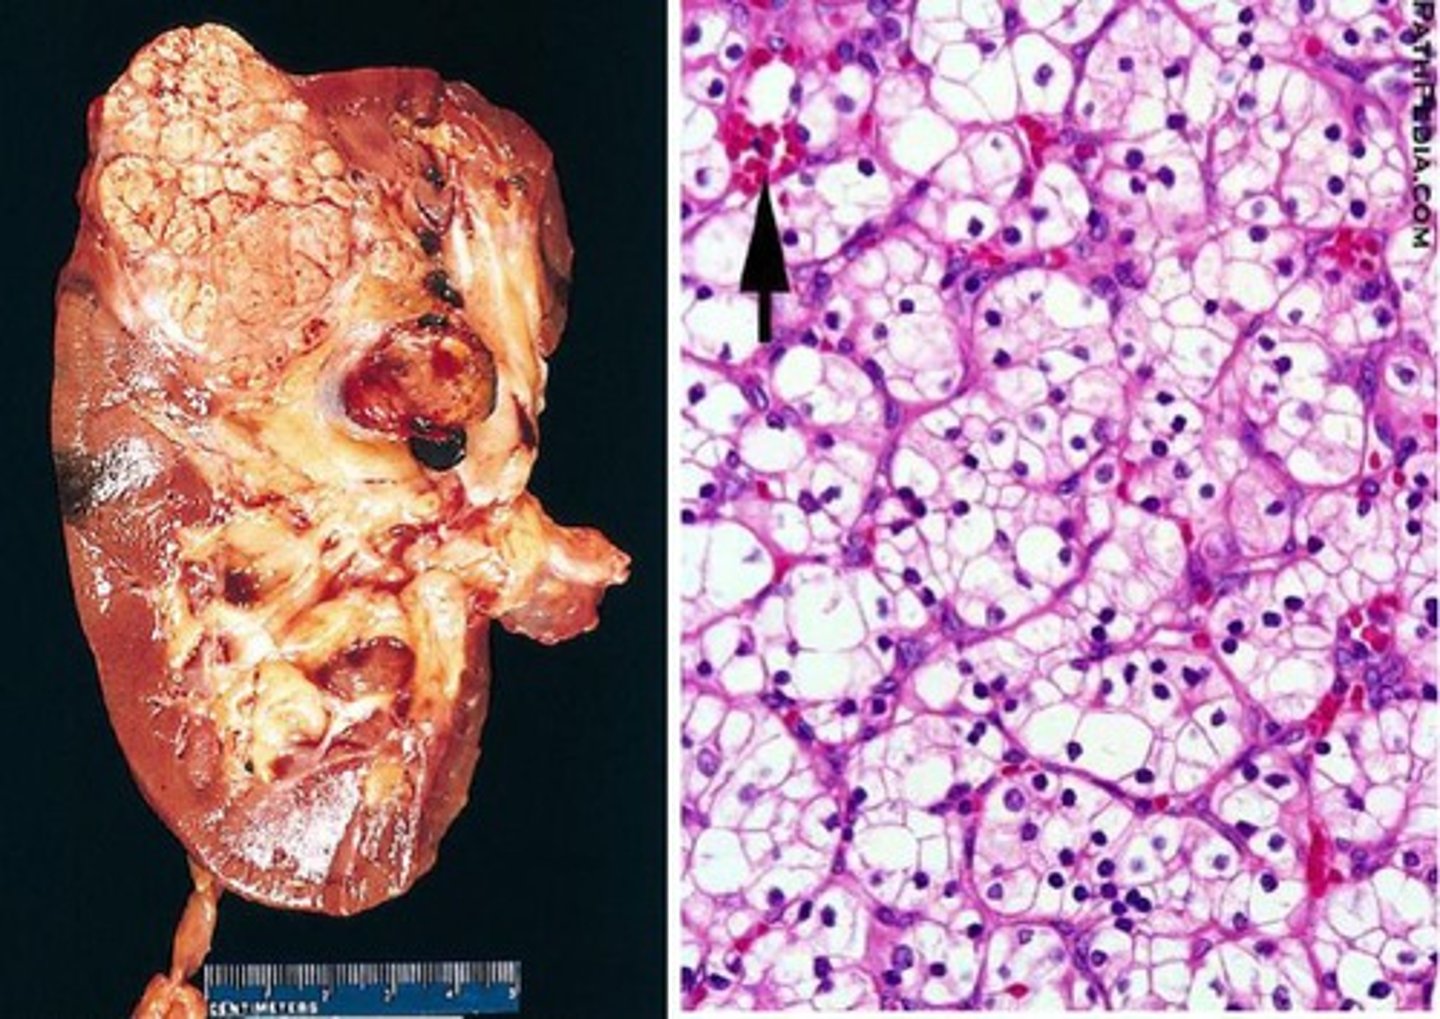

What are some possible RCC subtypes? Which is the most common?

Clear cell (most common), papillary, chromophobe, collecting duct, sarcomatoid